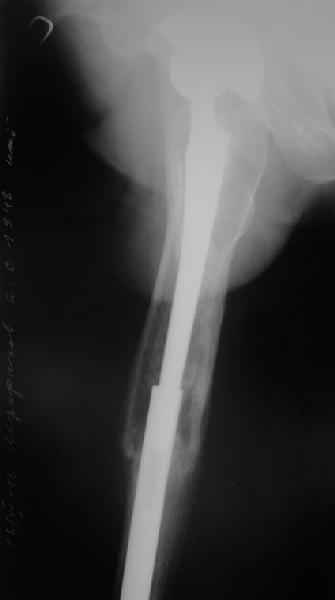

Уважаемые коллеги, в данном случае в лечении стандартного перипротезного перелома В2 Ванкуверской классификации (перелом вокруг ножки эндопртеза с потерей стабильности ножки при хорошем - не требующем пластики - качестве кости.Parvizi J, Rapuri VR, Purtill JJ, et al (2004) Treatment protocol for proximal femoral periprosthetic fractures. J Bone Joint Surg Am; 86-A Suppl 2:8-16)с успехом применён оригинальный, но малоизведанный способ лечения подобных повреждений. В результате и последующие рекомендации не могут быть стандартными. В подобных случаях, как это уже дискутировалось год назад, можно было выполнить ревизию длинной ножкой, во многом работающей как интрамедуллярный гводь + плюс кабель/серкляж в проксимальном отделе. Или, оставить имеющуюся ногу плюс длинная пластиа с кабелем/серкляжем, можно разными современными блокированными *примочками*. В таком случае при достижении консолидации пластина удаляется, тк при возникновении в будущем потребности в ревизии имеющийся дополнительный металл и без затруднит непростое вмешательство (кто пробовал, знает о чём я говорю). С длинной ногой, конечно, так же всё понятно. В данном случае мы имеем некую комбинацию, осложнённую отсутствием репозиции и фиксации в прошлом отломков вокруг ножки. Поэтому не каждый в данном случае рискнёт утверждать за счёт какого из компонентов системы - дистального либо проксимального обеспечивается стабильность. А если это и фиксация и за счёт ножки и за счёт гвоздя - каков баланс между данными компонентами в поддержании стабильности ситемы. То есть, я надеюсь, что дистального смещения ножки здесь не будет при условии сохранения как гвоздя, так и блокирующих винтов. При удалении же гвоздя возможна миграция ножки, только винтов - всей системы. Здесь же перелом (надеюсь, его не будет) блокирующих винтов может быть первым свидетельством механического неблагополучия системы... А так, помимо отличного результата этот случай так же косвенно подтверждает известную истину - Эндопротез, к сожалению, требует периодической замены. И выполняя фиксацию перипротезного перелома, а в последующем решая вопрос об удалении имплантатов, мы вынуждены думать и о функции сустава, и о том, как в будущем выполнить ревизию. Если ожидаемая продолжительность жизни пациента заставляет нас об этом думать. С уважением, Андрей

Сейчас опорную нагрузку на бедро берет на себя система от бедренного компонента эндопротеза до проксимального винта в интрамедуллярном гвозде. Свидетельство тому - реакция кортикала утолщением вокруг того самого винта. Таким образом вся кость от верхушки б.вертела до проксимального винта не испытывает физиологической осевой нагрузки. Результатом этого могут стать следующие последствия друг друга не исключающие: 1) все будет хорошо до перелома опорной системы по винту(ам) или в месте соединения штифта с ножкой или еще где-либо, 2) исключенная из-под нагрузки кость будет терять в количестве и качестве, что не очень (или очень не) хорошо для возможных будущих ревизий (тьфу-тьфу!!!).

Другой вариант перенести нагрузку на кость, "боем" проверив фиксацию ножки. Динамически заперев винт на 5мм ниже проксимального края овального отверстия. Статические винты отпереть, пациенту рекомендовать постепенно возрастающую дозированную нагрузку до полной в течение месяца. Хотя срок интеграции бесцементника считается 3 месяца(так пишут в руководствах и рекомендациях), если допустить, что ножка не интегрировалась. Появление клиники или проседание ножки по рентгенограмме даст ответ на счет того произошла ли интеграция или нет. С другой стороны проседание на 5 мм вряд ли приведет к чему либо серьезному, и если интеграции нет - рассматривать вопрос о ревизии. Если ножка интегрировалась, стрежень не удалять - для избежания перипротезных переломов.

Мне кажется, что гвоздь нужно отпирать в любом случае. По представленным Р-граммам судить о реинтеграции довольно сложно, здесь надо смотреть снимки без сжатия (или сделать КТ-МРТ в каком-нибудь "хитром" режиме).

Но вопрос даже не в этом, дольше ждать - не имеет смысла, если она вросла - то проблем не будет, если нет - то надо выполнить ревизию бедренного компонента. В условиях сросшегося перелома и нестабильной ножки это не будет проблемой, можно будет обойтись доступной стандартной ногой для первичной THA.

Если ждать дальше и дождаться stress shielding,то в условиях дефицита костной массы, малой кровью обойтись не удастся и результат будет менее прогнозируемым.